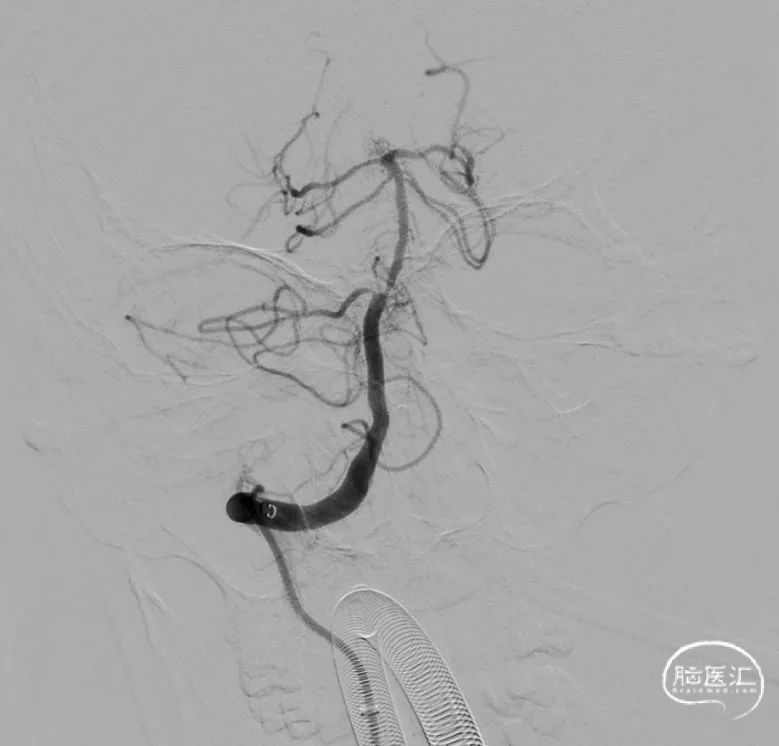

置入8F动脉鞘,黑泥鳅导丝带领5F单弯造影管行脑血管造影示左侧椎动脉纤细-V4段闭塞、右侧椎动脉优势-V4段闭塞,前向血流mTICI分级0级,基底动脉未见显影。

术前左侧椎动脉

术前右侧椎动脉

沿微导管送入通桥蛟龙®取栓支架 4*20mm,将取栓支架释放至基底动脉-右侧椎动脉,造影显示椎基底动脉再通。

基底动脉远端血栓,动脉内分次给予替罗非班4ml(1ml/min),应用SWIM技术回收通桥蛟龙®取栓支架 4*20mm,支架上可见鲜红色血栓。中间导管回抽通畅后,造影显示椎基底动脉再通。

微导丝再次通过V4段,送至右侧大脑后动脉P2段,沿微导丝送入球囊 2.0*12mm,球囊无法送至病变部位;遂更换Maverick球囊 2.0*15mm,将球囊送至狭窄处,以3atm充盈球囊扩张血管,持续20秒后抽瘪球囊,造影显示狭窄改善不明显。再次以相同方式6atm充盈球囊,持续约30秒后抽瘪球囊,造影显示狭窄明显改善。撤出微导丝及球囊,造影显示V4段狭窄改善,残余狭窄约30%,远端分支显影良好。观察10分钟后,造影显示无闭塞趋势,远端分支显影良好。